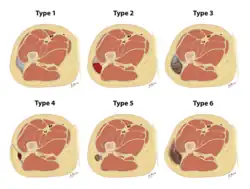

Drawings depicting the types of Morel-Lavallee lesions from the Mellando-Bencardino classification.

The Mellado-Bencardino classification can be used to describe a Morel-Lavallée lesion based on its MRI.[5] The classification categorizes the lesions into types.[8] The classification has six stages listed as Type I to Type VI.[5] The types do not align with specific treatments or outcomes.[4][8] The stages are based on multiple factors that can be observed on the lesion's MRI.[5] These factors include the following: the shape of the lesion, specific MRI features, and whether a capsule is present.[5][8]